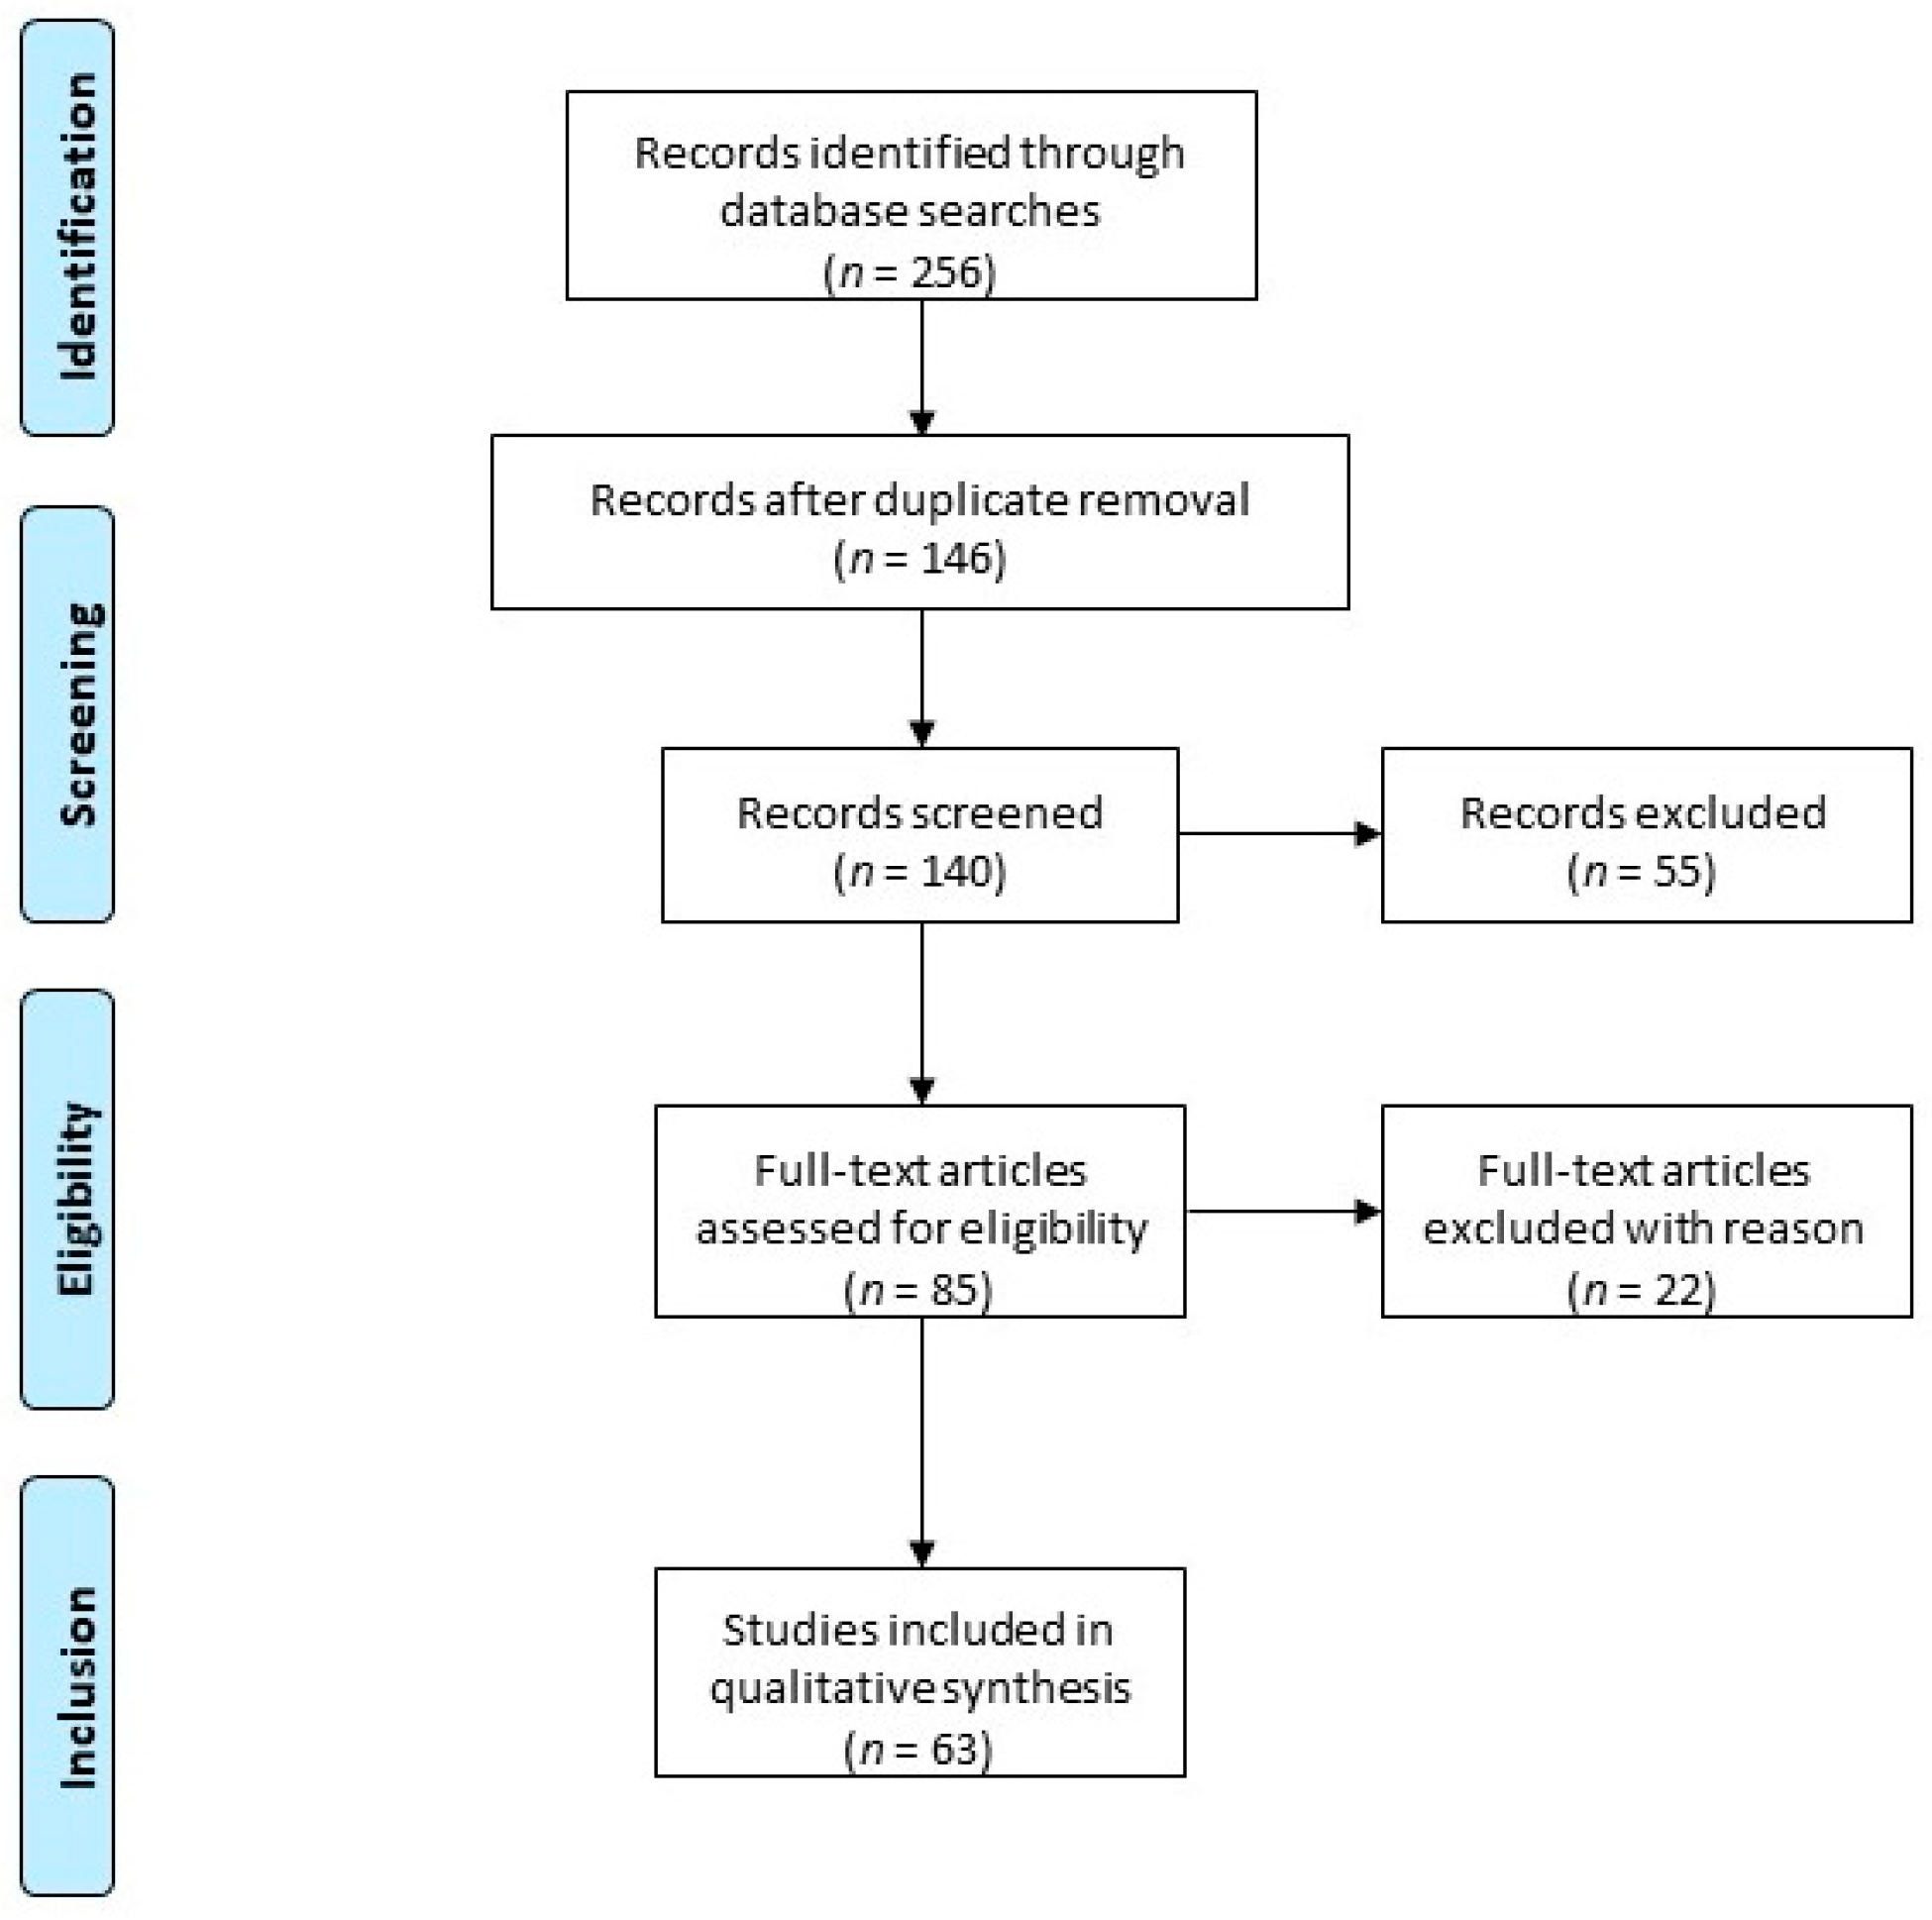

Uterine leiomyomas, current concepts: pathogenesis, impact on. Uterine leiomyoma at 10x magnification. Pathogenesis fig leiomyomas leiomyoma classification reproductive concepts procedural uterine surgical impact medical current management health figo